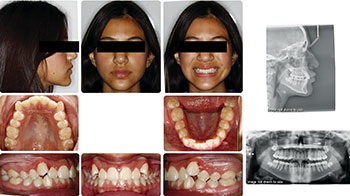

The first case is a 12-year-old female. Initially, the significant lingual inclination of her posterior teeth led me to believe that dental arch expansion would provide enough arch length to satisfy my non-extraction treatment plan. I didn’t invert upper incisor brackets as I didn’t think much negative torque would be needed after that expansion. However, her smiling side profile and the mid-treatment ceph from the pan/repo/ceph appointment at five months surprised me with the extent of the upper incisor proclination. At that point in treatment, I understood that a pivot was needed, and I felt confident that the appropriate use of negative torque and IPR would position her upper incisors where I wanted them to be within her face and smile. I decided to flip the upper incisor brackets at that same visit and progress with treatment, including IPR and engagement of the negative torque at subsequent appointments. She completed treatment in 18 months, achieving a favorable position of her upper incisors in her face and smile.